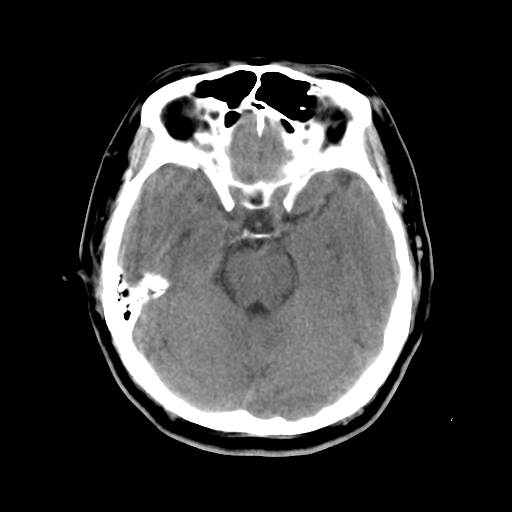

标题: CT15194:男,53岁,头痛、恶心三天。 [打印本页]

男,53岁,头痛、恶心三天。

上鼻道囊肿

筛窦粘液囊肿。

筛窦粘液囊肿

筛窦囊肿

筛窦囊肿、颅内未见明确异常

考虑筛窦内粘液囊肿可能性大。

支持左侧筛窦后组粘液囊肿。